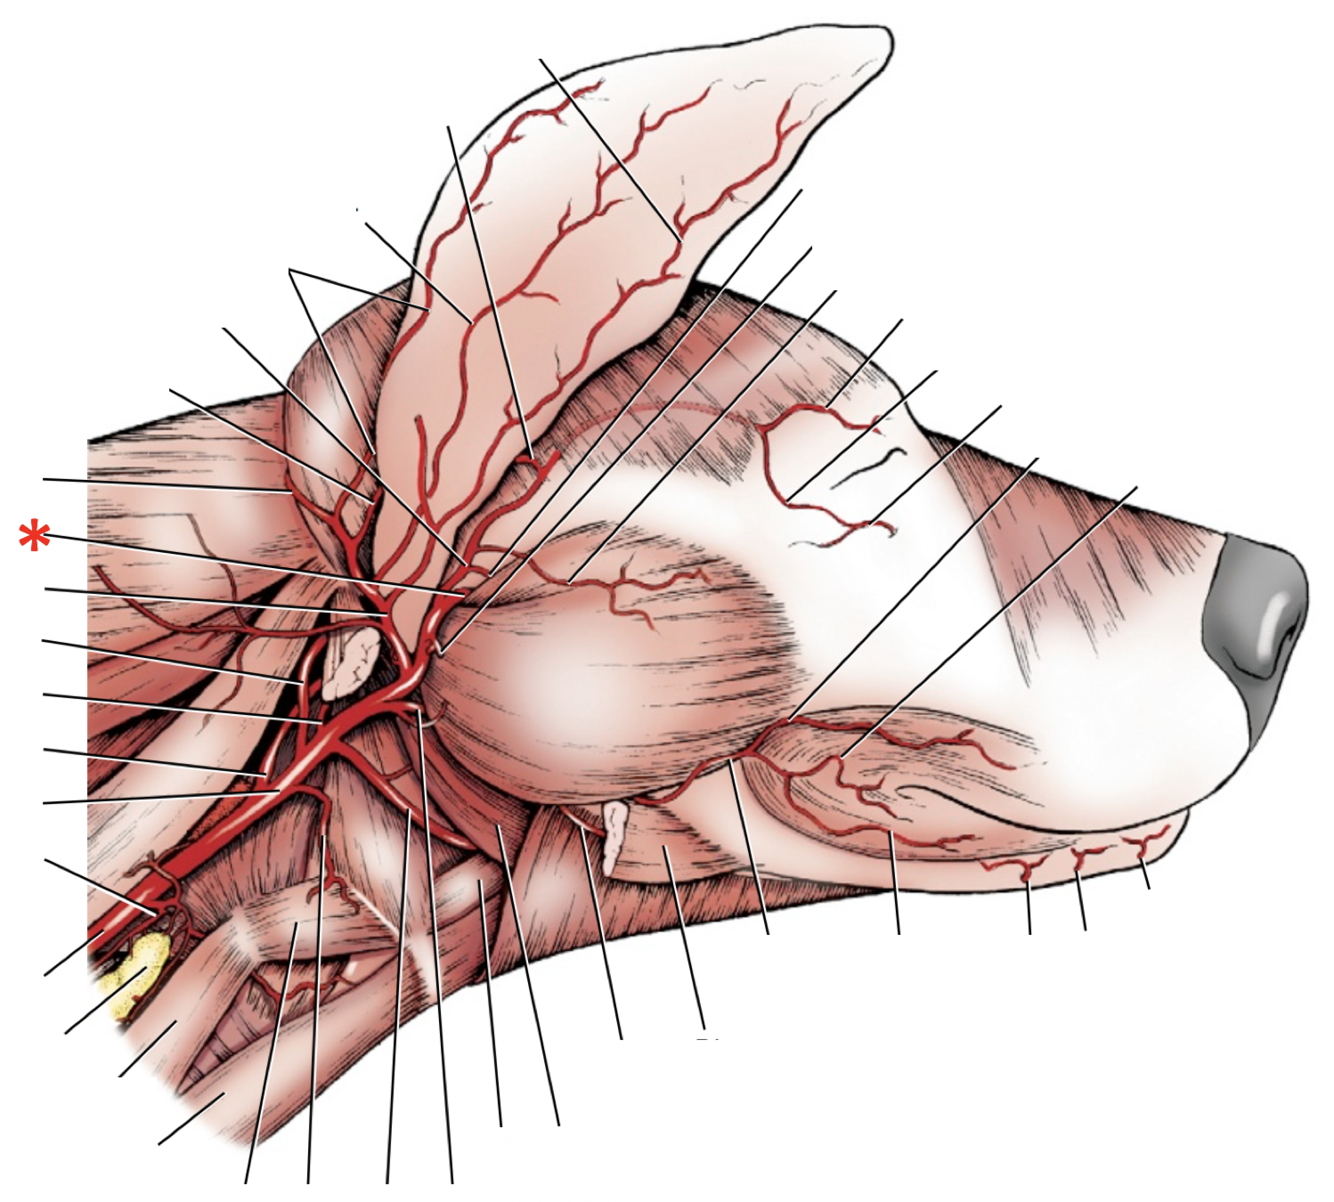

**A.** **facialis**

45

**A.** **lingualis**

46

**A.** **carotis** **externa**

47

**A.** **carotis** **communis**

48

**A.** **carotis** **interna**

49

1

**A. lingualis**

50

2

**A.** **laryngea** **cranialis**

51

**A.** **auricularis** **caudalis**

52

**A.** **maxillaris**

53

**N.** **laryngeus** **cranialis**

54

**Tr. vagosympathicus**

55

A

**Ggl.** **distale** **of n. vagus**

56

B

**Ggl.** **cervicale** **craniale** **of n.** **sympathicus**

57

**A.** **laryngea** **cranialis**